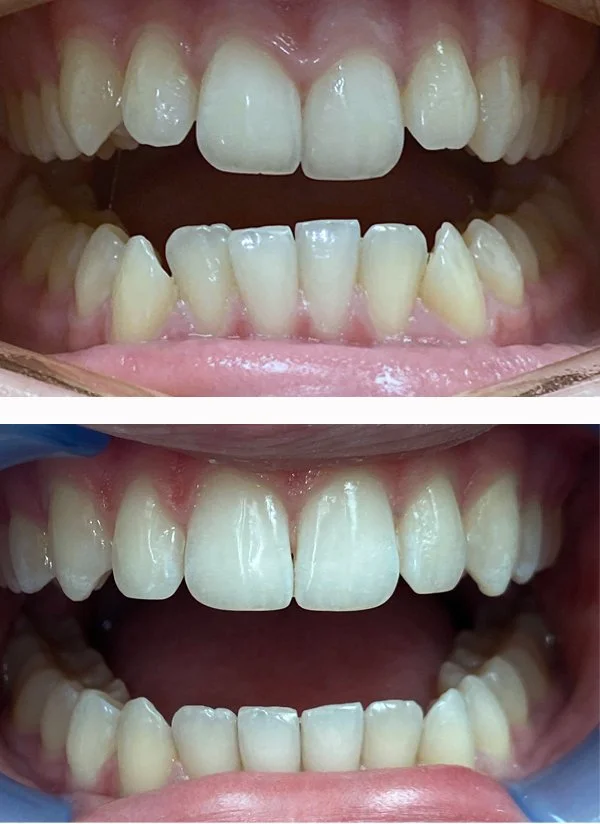

Soft Tissue Graft

We treat gum recession to enhance aesthetics, strengthen gum tissue, and provide better long-term support for teeth and dental implants.

Free Gingival Graft

Free Gingival Graft (premolars)